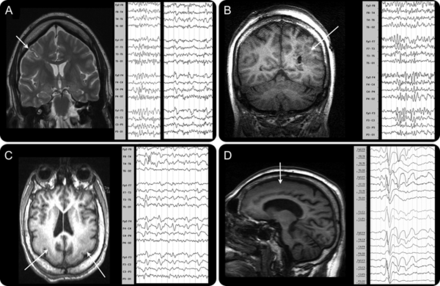

10例(77%),MRI异常(皮质畸形发展(MCD) 5)。这个组织的损伤变化很大程度上考虑到类似癫痫表型。焦发育和创伤性损伤是常见(图1中,得了)。1和3的病人,我们发现明确的结构性损伤,没有发现,一个重要的考虑因素在老年患者被宠坏的gradient-echo成像可能没有被反映在他们的早期,后来制度化和保守的管理。

发作放电。

总共有21个数据集从13个病人获得:一些有超过一种类型的痫性放电(见表)。大多数病人在其EEG-fMRI 1或2 IED分类识别研究。六个病人PFA记录分析和9 f (表)。焦点或多灶2例大幅波被确定。对于每一个主题,我们计算的总时间在研究癫痫样的事件。这样做是通过测量每个事件的持续时间明显的脑电图和添加这些时光。研究与频繁的事件有很多秒的事件分析、研究和罕见的事件可能只有几秒钟的数据痫性活动发生(表;还列出的数字)。

焦点和边音的放电。

焦简易爆炸装置被记录在2例(4和11如图依照病人)。两个独立的焦点是记录在病人4(一左一右)。局部放电与皮质激活相关的整合与简易爆炸装置。

前两个病人、胼胝体(病人4和11,图4)。在这些患者中,PFA排放不定地显示正确,或者发出强调。这些边音的PFA排放相应产生的单侧性的招聘网络上面描述。